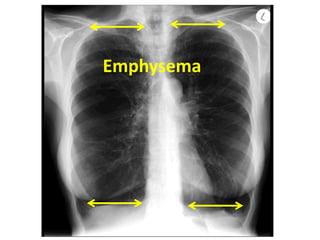

Emphysema